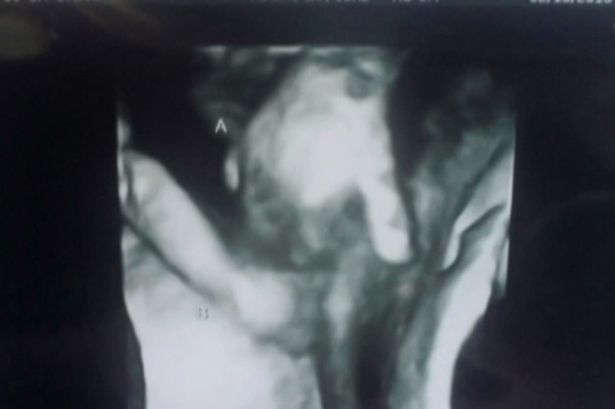

A heartfelt baby scan image of a dying twin holding his unborn sister’s hand inside the womb has emerged online.

But a baby scan picture has given the parents an unexpected piece of comfort as it appears to show the unborn twins looking after each other in the womb.

“We didn’t really see much, she said there’s his hand and there’s her hand and it looks like they’re holding hands.Most twins when she’s trying to take pictures and stuff, they’re kicking each other and hitting each other, and she said with our twins, it seems like she was very protective over him.

The boy twin, who the parents have named Mason, is on the left and has appears to have his hand wrapped around the finger of his sister, Madilyn.